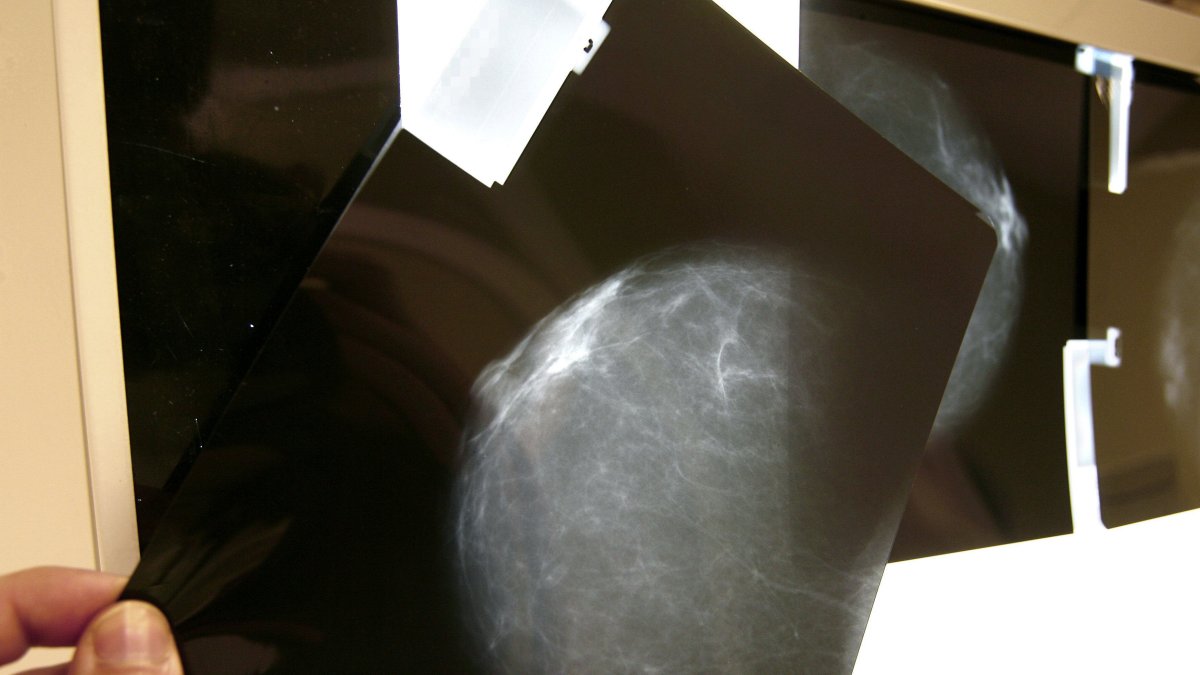

La Comisión Europea lanzó este lunes 23 de enero de 2023 una iniciativa para crear una plataforma digital europea que conectará recursos y bases de datos de imágenes del cáncer en toda la Unión Europea, con el fin de favorecer la investigación y mejorar el diagnóstico y la atención personalizada al paciente, también con la participación de pymes especializadas en inteligencia artificial (IA).

Está previsto que el diseño y los mecanismos de colaboración de la nueva infraestructura digital paneuropea, bautizada Iniciativa Europea de Imagenología del Cáncer, se hayan completado el próximo diciembre para que entonces puedan conectarse los proveedores de datos, informó el Ejecutivo comunitario al anunciar hoy en un evento en Bruselas este proyecto emblemático del Plan Europeo "Vencer al Cáncer".

La futura plataforma tendrá su primer prototipo a finales de 2024 con la previsión de disponer de la versión final un año después y que esté plenamente operativa en 2026, añadió Bruselas.

El objetivo primordial de la nueva infraestructura será ayudar a los proveedores de asistencia sanitaria, los institutos de investigación e investigadores a hacer el mejor uso posible de soluciones innovadoras basadas en datos para el tratamiento y la atención del cáncer, incluida la inteligencia artificial.

Esas herramientas son el proyecto EUCAIM, que desplegará la infraestructura para incluir en la plataforma más de 100.000 casos de cáncer para 2025 y al menos 60 millones de imágenes de cáncer, y el Dispositivo de Ensayo y Experimentación de IA para la Salud (TEF- Health), que permitirá a las pequeñas y medianas empresas que hayan desarrollado soluciones de inteligencia artificial para el tratamiento del cáncer probarlas en entornos reales.